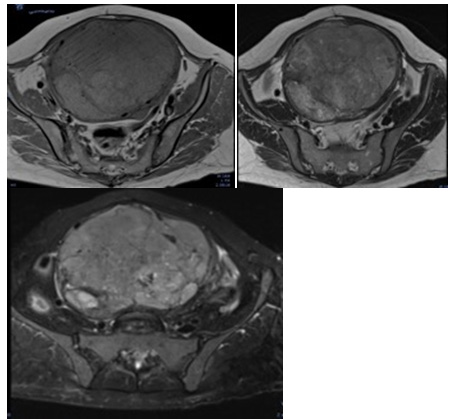

Magnetic resonance imaging 11.30.2021 uterus with loss of morphology, with the presence of an intramural fibroid of 16x11x16 cm, with areas of hyaline degeneration (Image 2) (Image 3).

Image 3 MRI of the simple pelvis. It is observed in axial plane sequence T1, image dependent on uterus iso intense to the muscle and with areas of solid appearance and some of cystic appearance in T2 (Image 4) and incipient areas of fat content (white arrow) in SEQUENCE FAT SAT (Image 5).